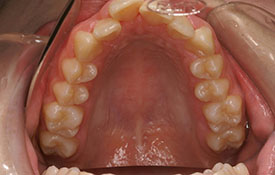

叢生|ブラケットを用いた治療

CASE 1

CASE 2